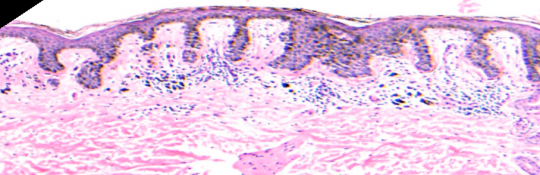

VA40: Right Upper Arm, Compound Melanocytic Nevus, Clarks